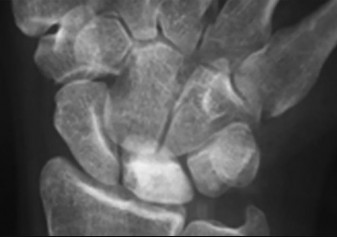

- الأشعة السينية (X-rays): هي الخطوة الأولى في تقييم الكسور، الخلوع، وتغيرات التهاب المفاصل. تساعد في تحديد مدى تدهور العظام والمسافات المفصلية. على سبيل المثال، تُظهر صور الأشعة السينية كسور السلاميات

أو كسور قاعدة العظم المشطي الخامس

، بالإضافة إلى علامات مثل "الدمعة الشعاعية" (Radiographic Teardrop) في الرسغ التي تمثل الزاوية الزندية الراحية الحرجة للكعبرة البعيدة

. - الأشعة المقطعية (CT Scan): توفر صوراً تفصيلية ثلاثية الأبعاد للعظام، وهي مفيدة جداً لتقييم الكسور المعقدة، مثل كسور العظم الخطافي (Hamate Hook Fracture) التي قد لا تظهر في الأشعة السينية العادية